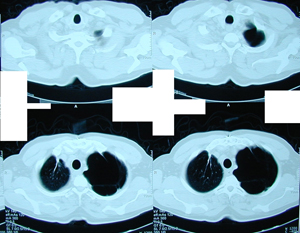

Εικόνα 5 α-γ

Μετεγχειρητική αξονική τομογραφία του θώρακος σε διαφορετικά επίπεδα. Φυσιολογική εικόνα του δεξιού πνεύμονος ενώ παραμένει αμετάβλητη η εικόνα του αριστερού πνεύμονος με τις εμφυσηματικές φυσαλίδες και ευμεγέθεις αερώδεις κύστες.

Α-Β

Γ